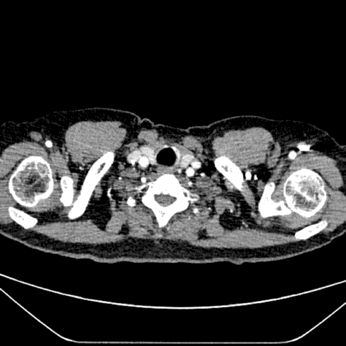

术后随访

患者于出院前行CTA检查,结果显示,动脉瘤隔绝良好,无内漏;分支支架通畅,形态良好;椎动脉供血良好。

术后三维重建/CTA